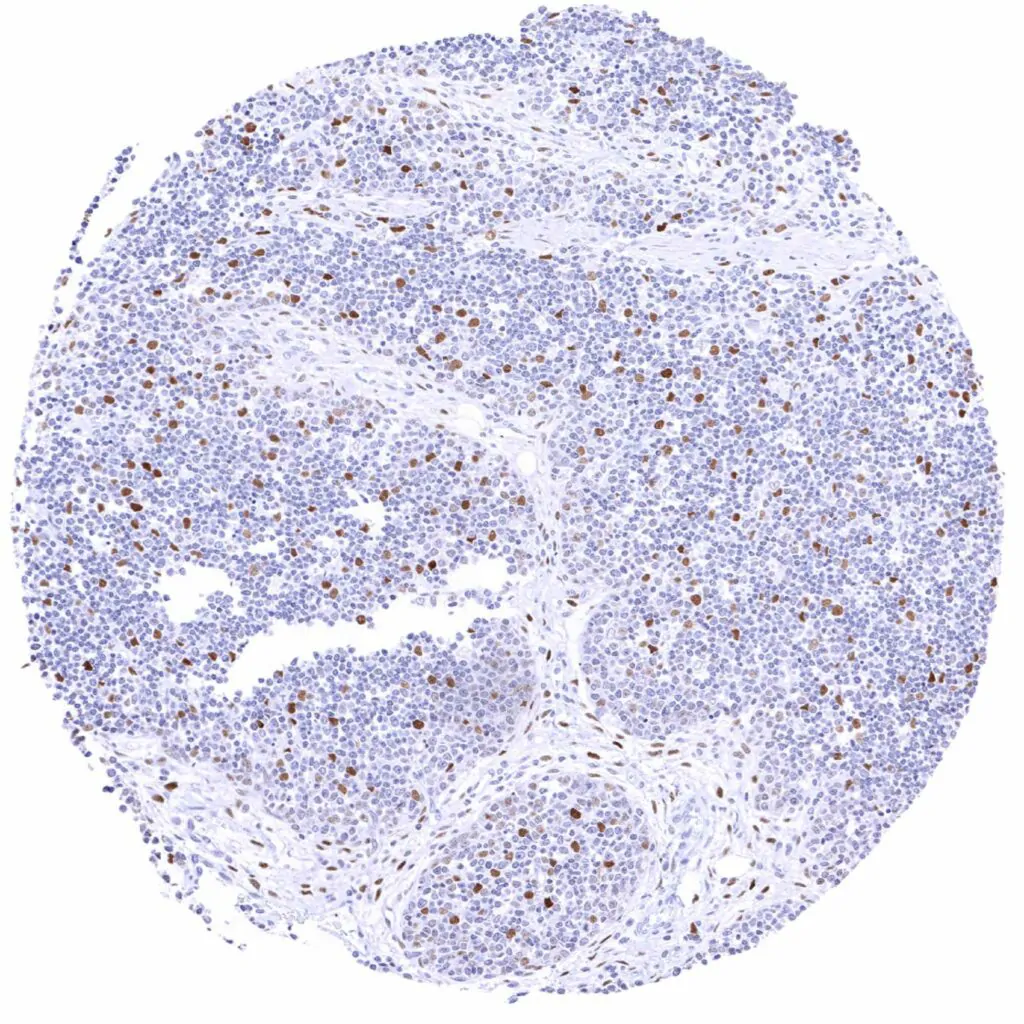

Tonsil – Weak to moderate Cyclin E1 staining of a fraction of lymphocytic cells, especially in germinal centres